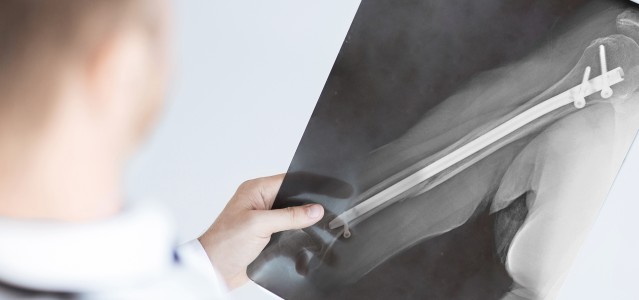

During surgery, the doctor drills a hole into the medullary cavity of a broken bone and then inserts a long titanium IM nail into the hole. The nail is then screwed into place, holding the broken pieces together securely so they can heal properly.